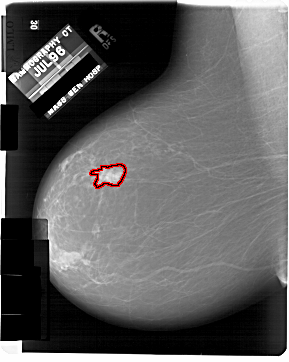

A_1933_1.LEFT_MLO

FILE: A_1933_1.LEFT_MLO.OVERLAY

TOTAL_ABNORMALITIES 1

ABNORMALITY 1

LESION_TYPE MASS SHAPE IRREGULAR MARGINS MICROLOBULATED

ASSESSMENT 5

SUBTLETY 5

PATHOLOGY MALIGNANT

TOTAL_OUTLINES 1

BOUNDARY